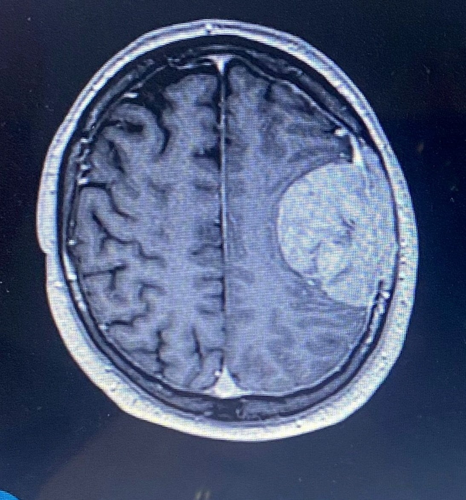

He was blue-lighted to Southmead Hospital, Bristol, where a CT scan revealed a .

Stuart's speech fluctuated, and he was diagnosed with a meningioma - a slow-growing tumor.

By TalkerAfter being blue-lighted to Southmead Hospital, a CT scan revealed that Stuart had a mass on the brain.

Stuart’s speech fluctuated, and he was prescribed steroids. Surgeons advised that, because there was no evidence of cancer elsewhere, it was likely to be a  that Stuart could have had for years.Â

It had not grown into his brain but was attached to the membrane and skull, part of which had to be removed and reconstructed using bone cement.

Although initial scans suggested only normal post-surgical swelling, a subsequent MRI report revealed Stuart had .